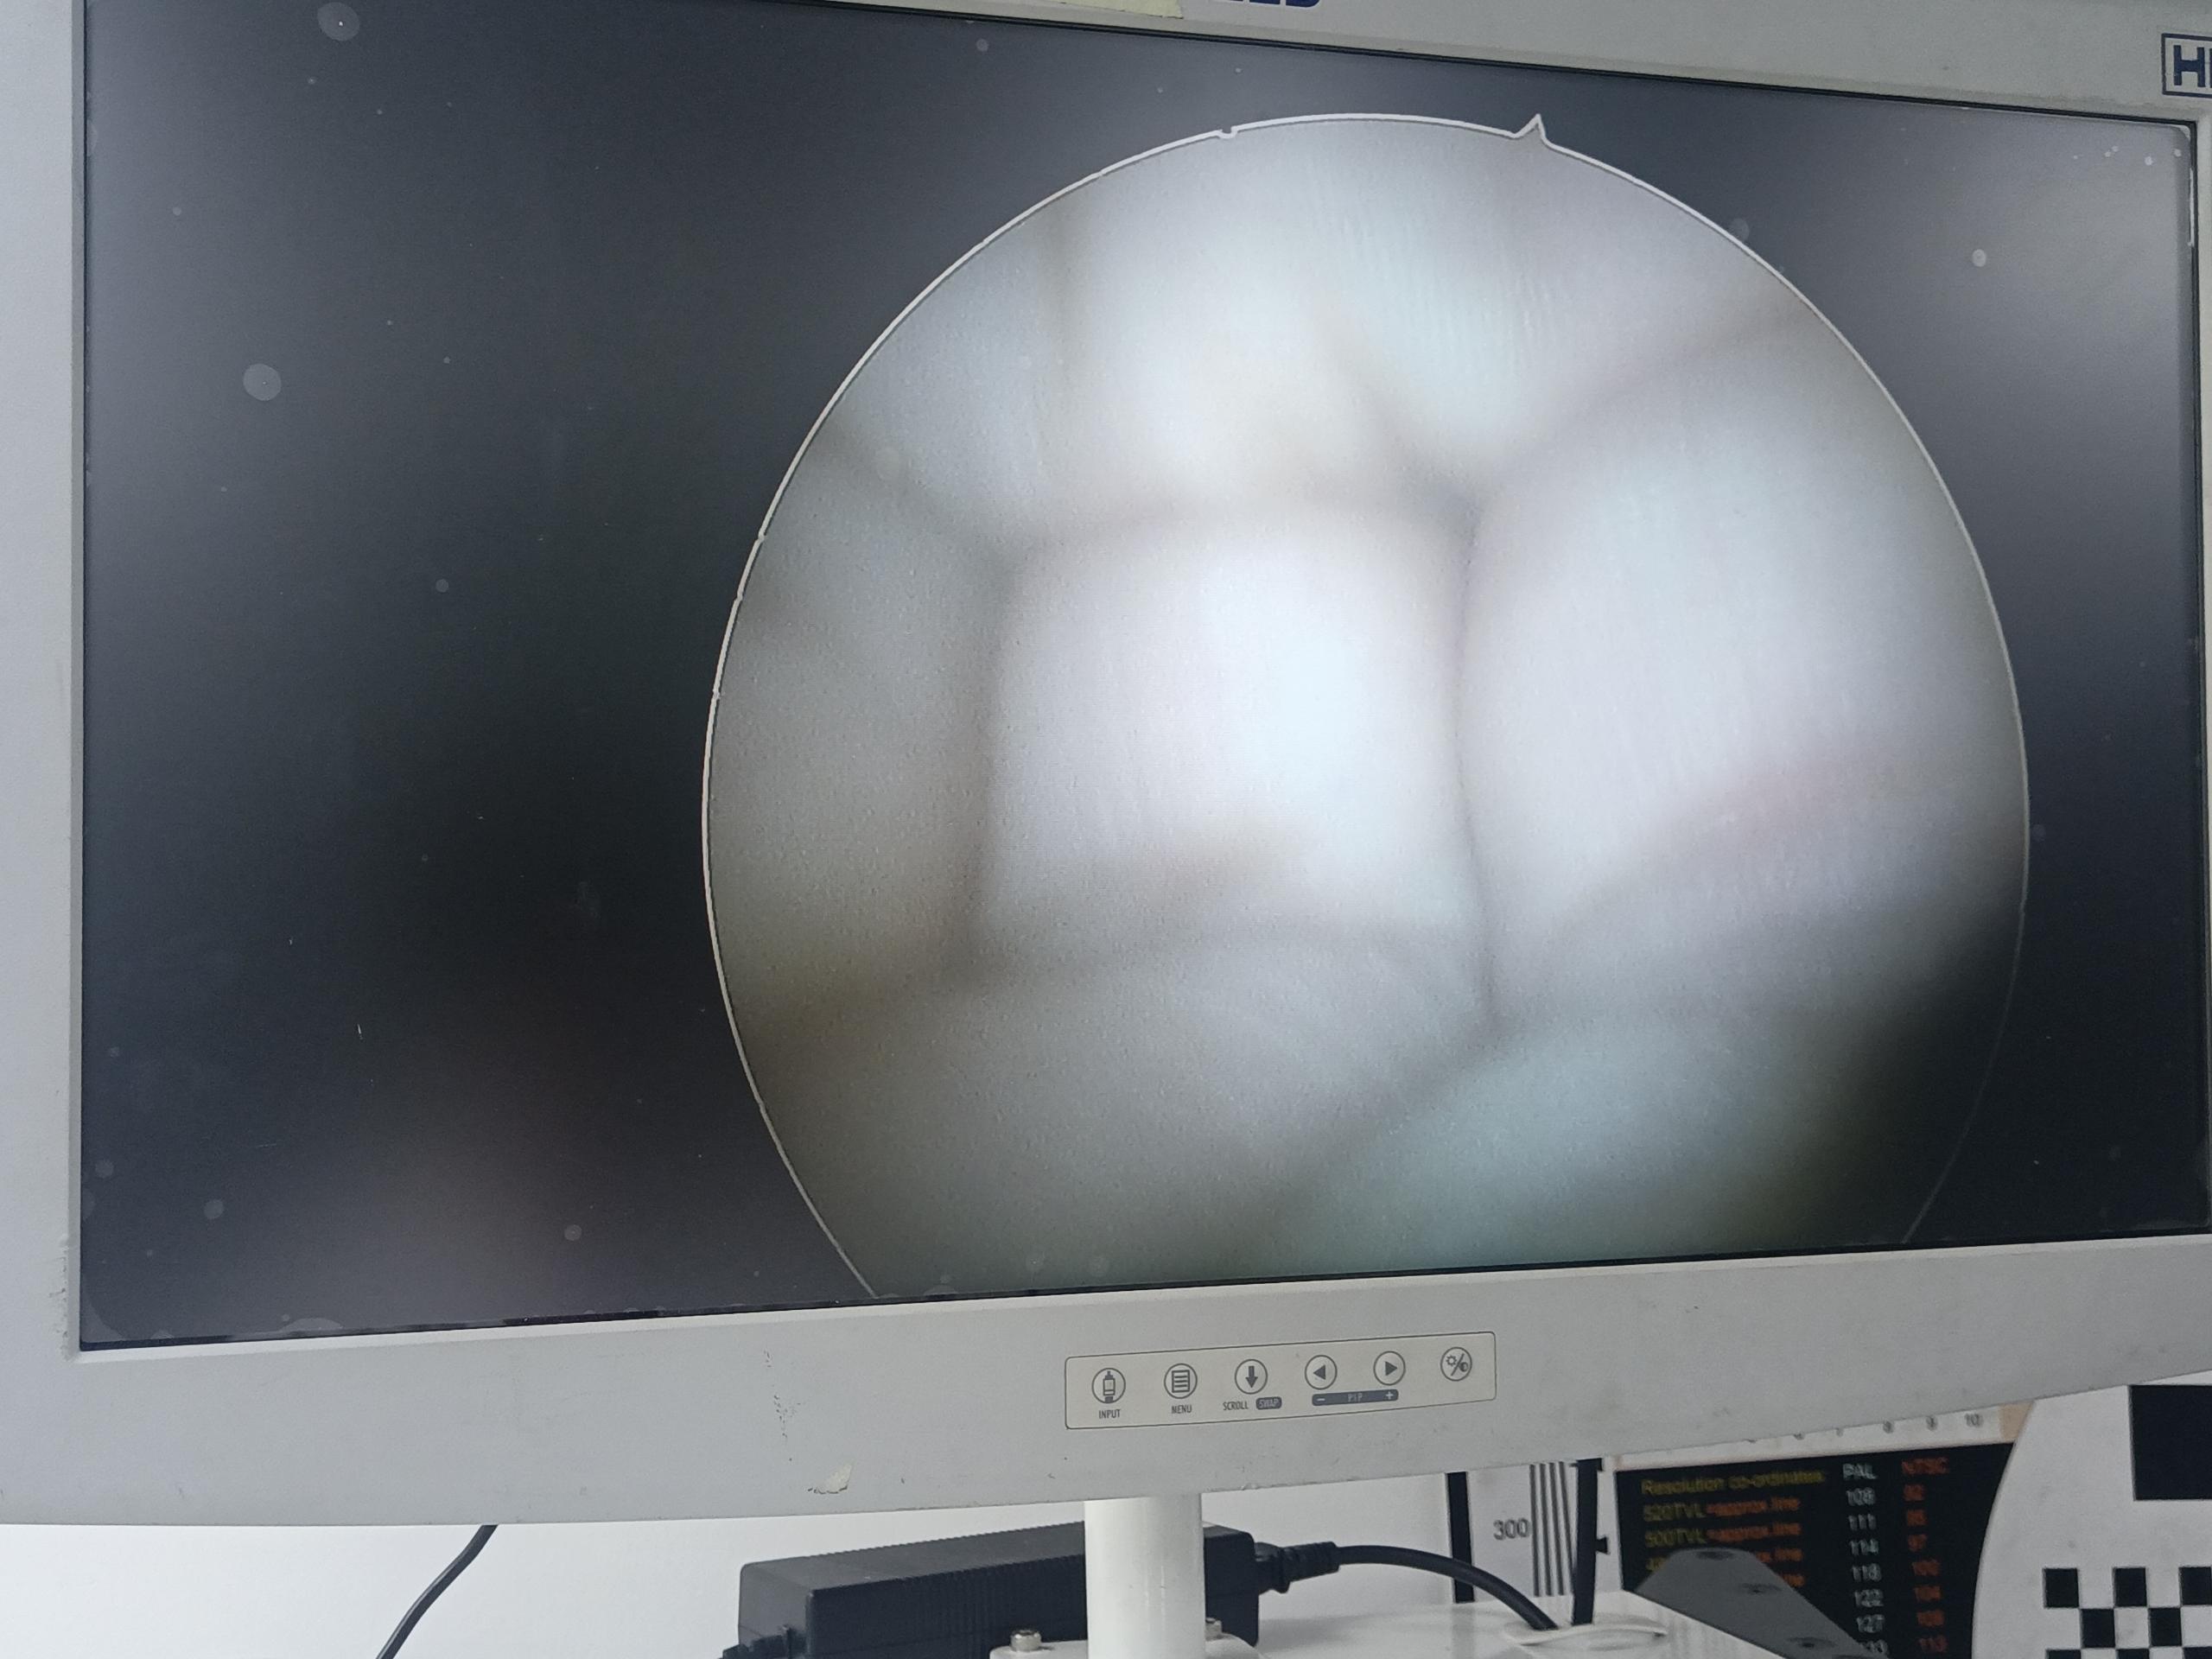

| 故障內(nèi)容 | 圖像模糊,物鏡破損,漏水腐蝕,棒透鏡腐蝕,圖像偏移 |

| 維修方案 | 更換物鏡,更換棒透鏡 ,校對(duì)圖像,內(nèi)窺鏡抗震蕩抗沖擊性能測(cè)試,內(nèi)窺鏡密封性性能檢測(cè);內(nèi)窺鏡抗震蕩性能測(cè)試,內(nèi)窺鏡冷熱沖擊性能檢測(cè)。 |